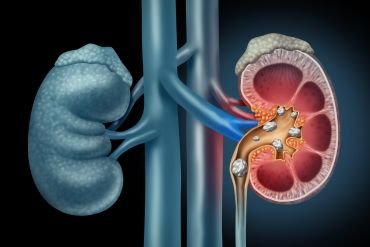

Kidney Stones

Kidney stones are composed of various substances, including calcium, oxalate, and uric acid. The size of these stones can range from a grain of sand to a golf ball. Understanding the composition of kidney stones is essential for effective treatment.

Kidney stones are composed of various substances, including calcium, oxalate, and uric acid.